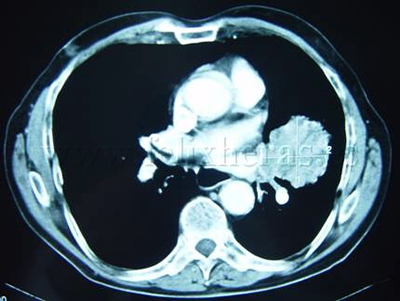

Cáncer de pulmón